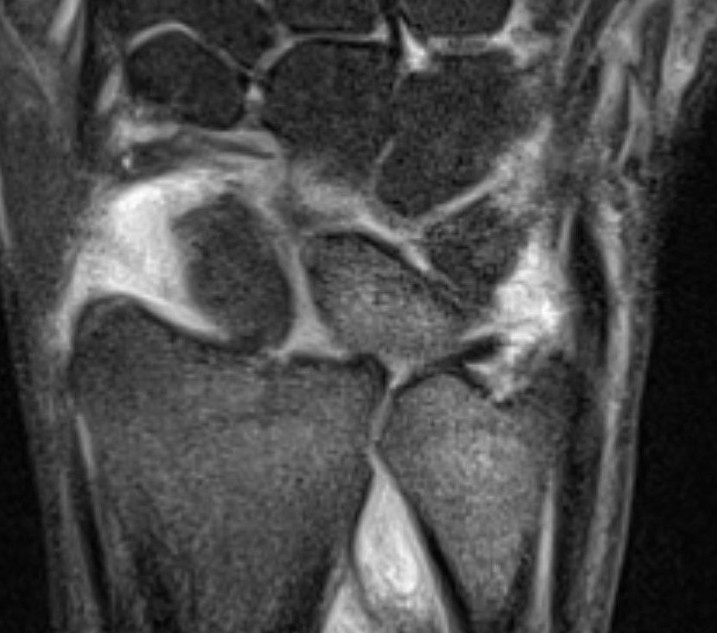

MRI

MRI demonstrating dorsal distal ulna subluxation associated with significant ligament disruption